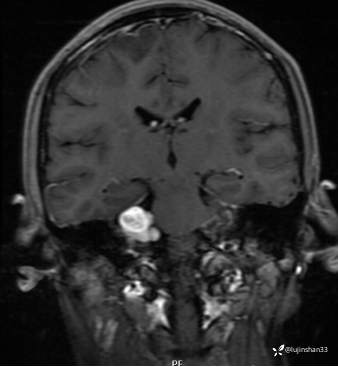

第一次术前颞骨CT及MRI:

第二次术前CT及MRI

临床诊断: 1.听神经瘤(右)2.神经纤维瘤病2型 3.左耳听神经瘤术后